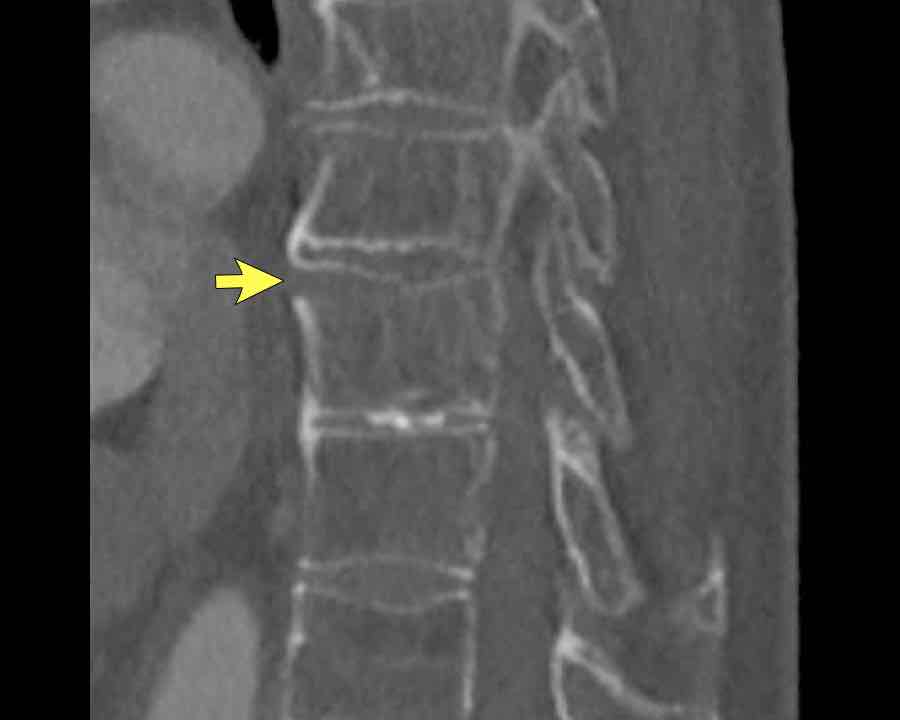

Scroll through images.

What are the findings?

Findings

- C injury? No.

- Signs of a rigid spine?

Yes, so be aware of potentially very subtle B3 injury. - A subtle fracture on the anterior vertebral body is seen (arrows).

Conclusion

Injury type B3.